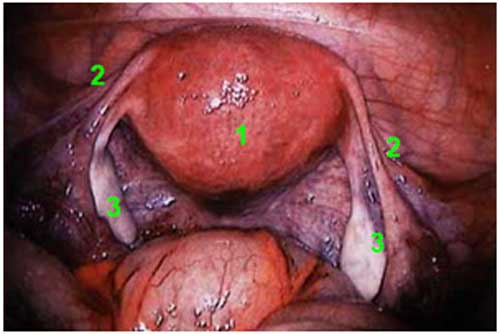

Laparoscopy uses an instrument called a laparoscope to look at the abdominal organs. A laparoscope is a long, thin tube with a high-intensity light and a high-resolution camera at the front. The instrument is inserted through an incision in the abdominal wall. As it moves along, the camera sends images to a video monitor.

Laparoscopy allows your doctor to see inside your body in real time, without open surgery. Your doctor also can obtain biopsy samples during this procedure.

When the procedure is part of fertility testing, the doctor is evaluating the structures of the reproductive system, including the ovaries, fallopian tubes, and uterus.